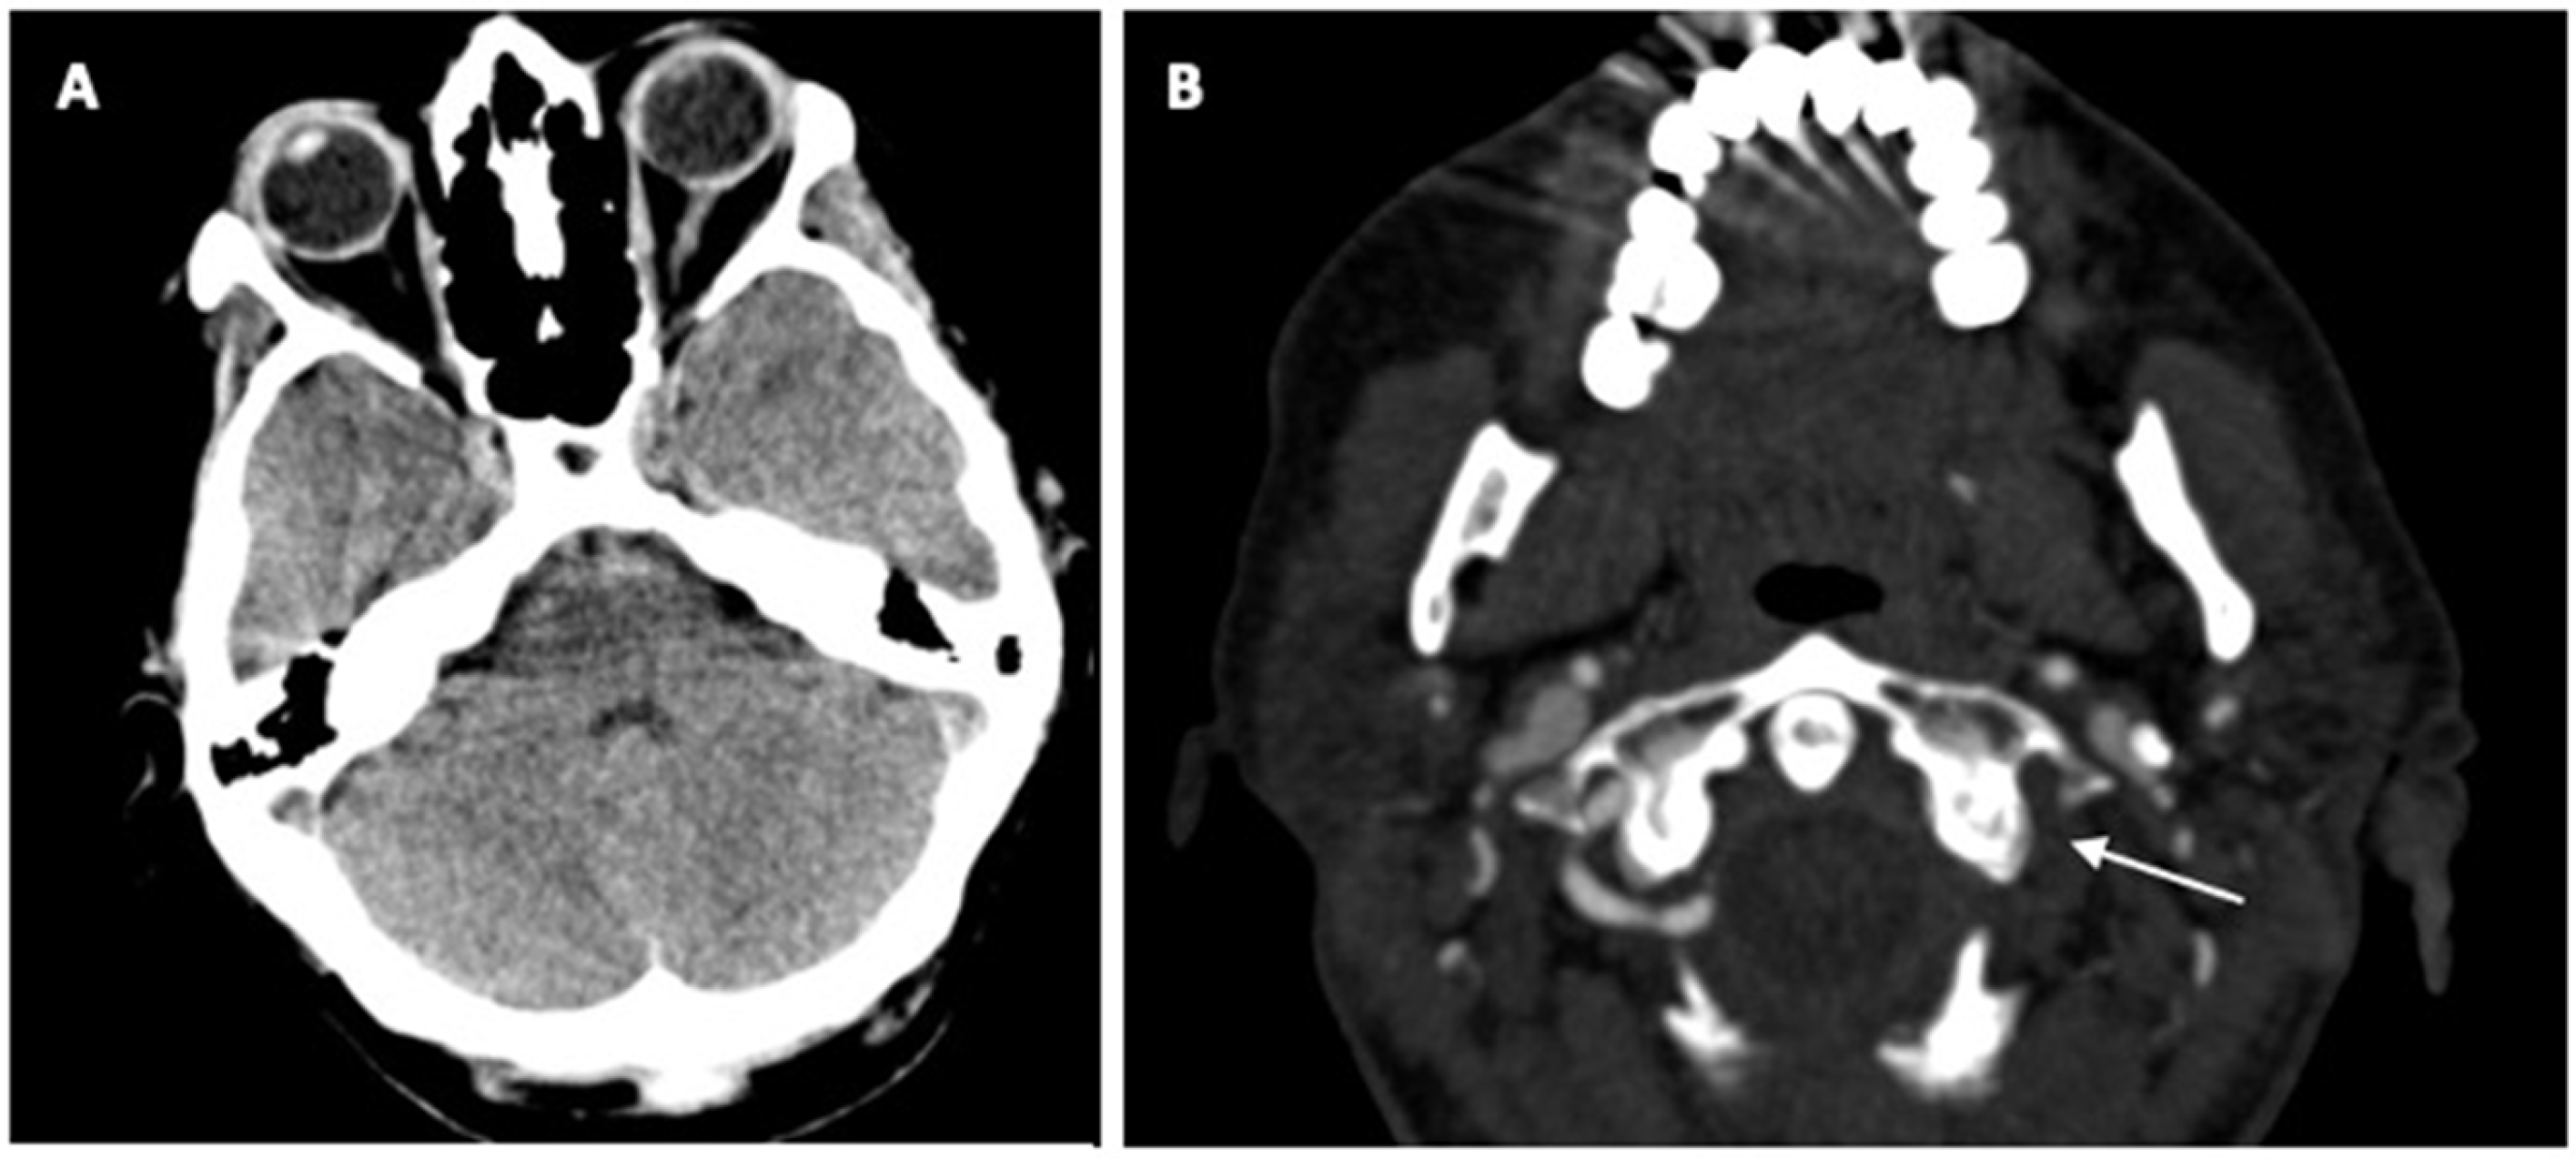

2. Case Report